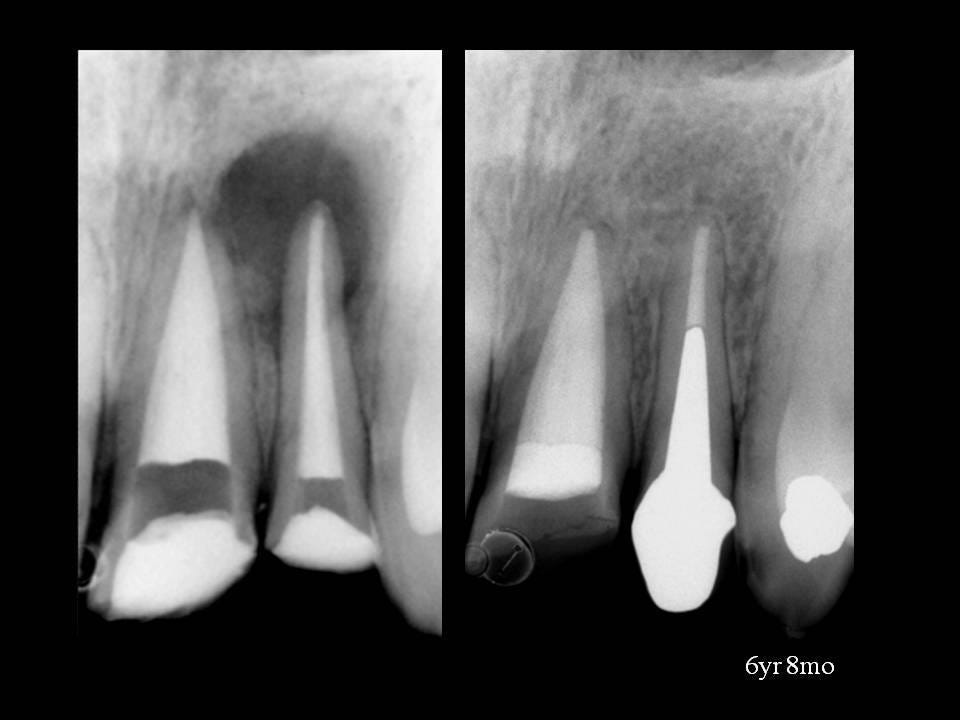

Periapical radiographs before, during,and after endodontic treatment of Apical Limit And Working Length In Endodontics — in this paper, we review the different schools of thought for working length determination, and how. — thus, the predictable endodontic success demands an accurate working length determination of the root canal. in this paper, we review the different schools of thought for working length determination, and how apex locators work and how they. —. Apical Limit And Working Length In Endodontics.

A) Coronal access; B) Apical periodontitis and apical root resorption Apical Limit And Working Length In Endodontics — this paper reviews the different schools of thought for working length determination, and how apex locators. establishing the working length is an important step in endodontic treatment as inaccurate length determination may lead. — establishing the working length is an important step in endodontic treatment as inaccurate length determination may. in this paper, we review. Apical Limit And Working Length In Endodontics.